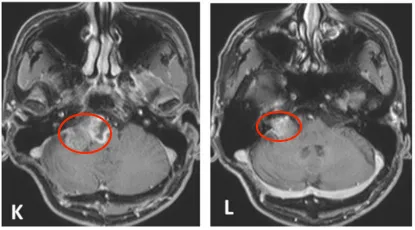

2004年4月初始MRI显示右侧桥小脑角区肿瘤不均匀强化。2005年8月首次术后、伽玛刀治疗前影像资料记录肿瘤状态。2007年5月第二次术前MRI评估显示肿瘤进展,术后一个月影像确认切除范围。

定期随访影像资料(图1 E-J)完整记录2008-2013年肿瘤变化情况。2013年末至2014年初复查显示肿瘤再次生长,2014年4月术前MRI显示肿瘤不均匀强化伴脑干受压。术后两个月随访影像确认次全切除结果。